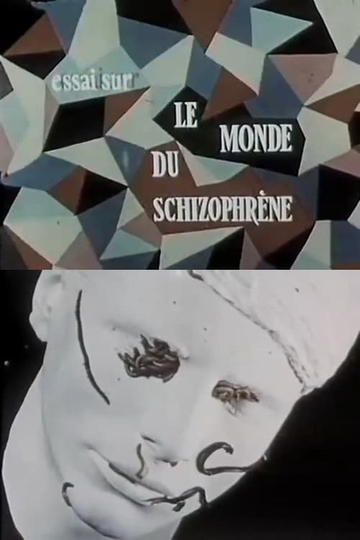

His notable works include Le Psychodrame (1961), which explores psychodrama therapy, and La Schizophrénie (1965), a documentary on schizophrenia. Duvivier's films are recognized for their informative content and compassionate portrayal of mental health issues.